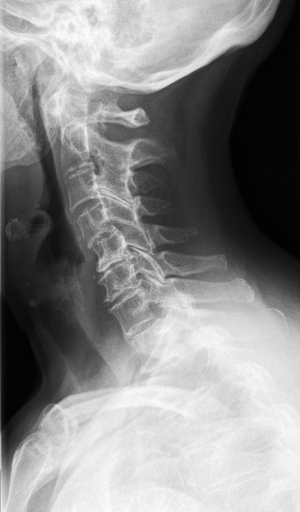

The IRMA dataset, supplied for the imageCLEF organization, had annotated codes were similar to domain expert knowledge [9, 12, 13, 14]. This database has been used by many researchers and is comprised of preset test and training portions, which enable direct comparisons of metrics. The IRMA codes (manually created by several clinicians) contains information on technical, biological and diagnostic traits of the image in a structured manner: TTTT-DDD-AAA-BBB. Each section is hierarchical meaning there is a least significant bit and most significant digit (Table 1). Sample IRMA images are depicted in Fig. 1.